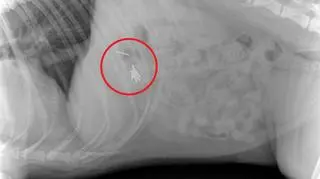

Zdjęcie RTG brzucha psa

Źródło: Uniwersyteckie Centrum Medycyny Weterynaryjnej

Na początku tygodnia ofiarą kiełbasek padła Najra. Pies przebywał na ogrodzonej działce, kiedy najadł się gwoździ. Natychmiast został przewieziony do kliniki weterynaryjnej, gdzie zrobiono mu zdjęcie RTG jamy brzusznej. Jak się okazało, Najra miała w sobie siedem gwoździ. Konieczna była operacja.